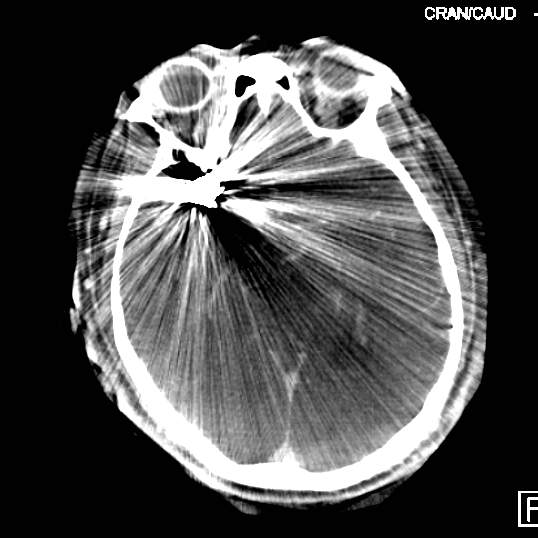

病史:中年女性,新冠感染,颅内动脉瘤破裂,Hunt-Hess 4级